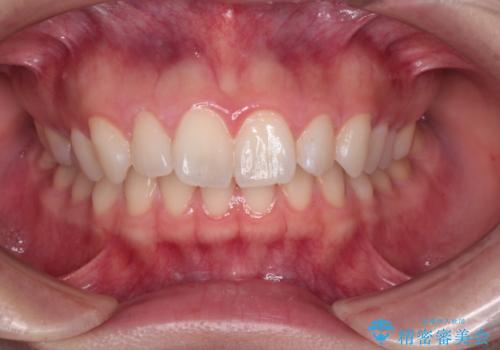

抜歯矯正をインビザラインで実現

- 患者様は、上下顎の歯列不正と前歯部の突出感を主訴としてご来院されました。診断の結果、上顎左右第一小臼歯を抜歯することでスペースを確保し、歯列全体を整える方針としました。本来はワイヤー矯正が推奨されるケースですが、患者様のご希望により、透明なマウスピース型矯正装置「インビザライン」を使用した治療計画を立案しました。治療期間は約3年で、奥歯の噛み合わせを維持しながら、徐々に前歯の位置を整えました。